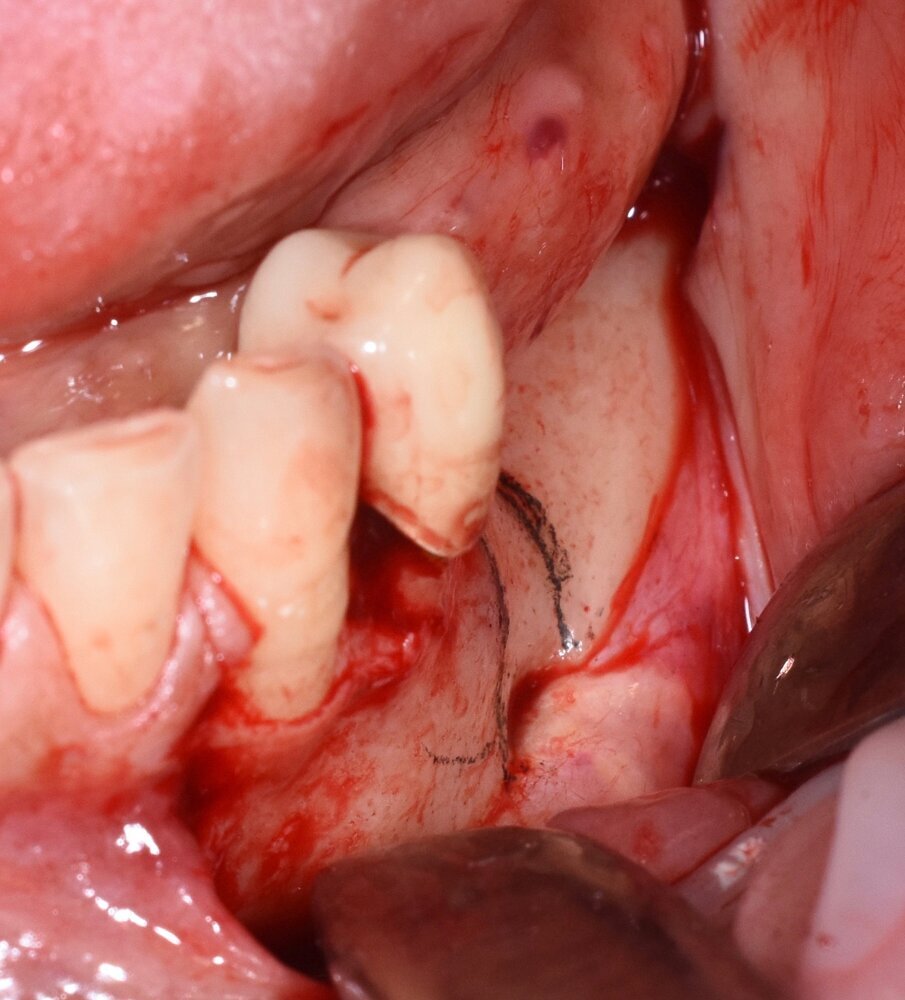

Fig. 3 - Visione iniziale laterale.

Fig. 6 - Taglio osteotomico eseguito con inserto piezoelettrico.